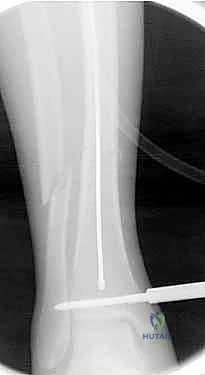

بعد ذلك، يتم إدخال سلك دليلي معدني رفيع داخل القناة النخاعية، يليه استخدام أدوات توسيع دقيقة (Reamers) لتنظيف وتوسيع القناة وتجهيزها لاستقبال المسمار. هذه الخطوة بحد ذاتها تحفز نمو العظم من خلال نشر الخلايا العظمية داخل القناة.

4. إدخال المسمار النخاعي والتثبيت النهائي

يتم تمرير مسمار التيتانيوم بدقة داخل العظم. وبمجرد التأكد من موضعه المثالي بالأشعة، يقوم البروفيسور هطيف بإدخال المسامير التشابكية (Locking Screws) العرضية في أعلى وأسفل المسمار لضمان التثبيت المطلق.